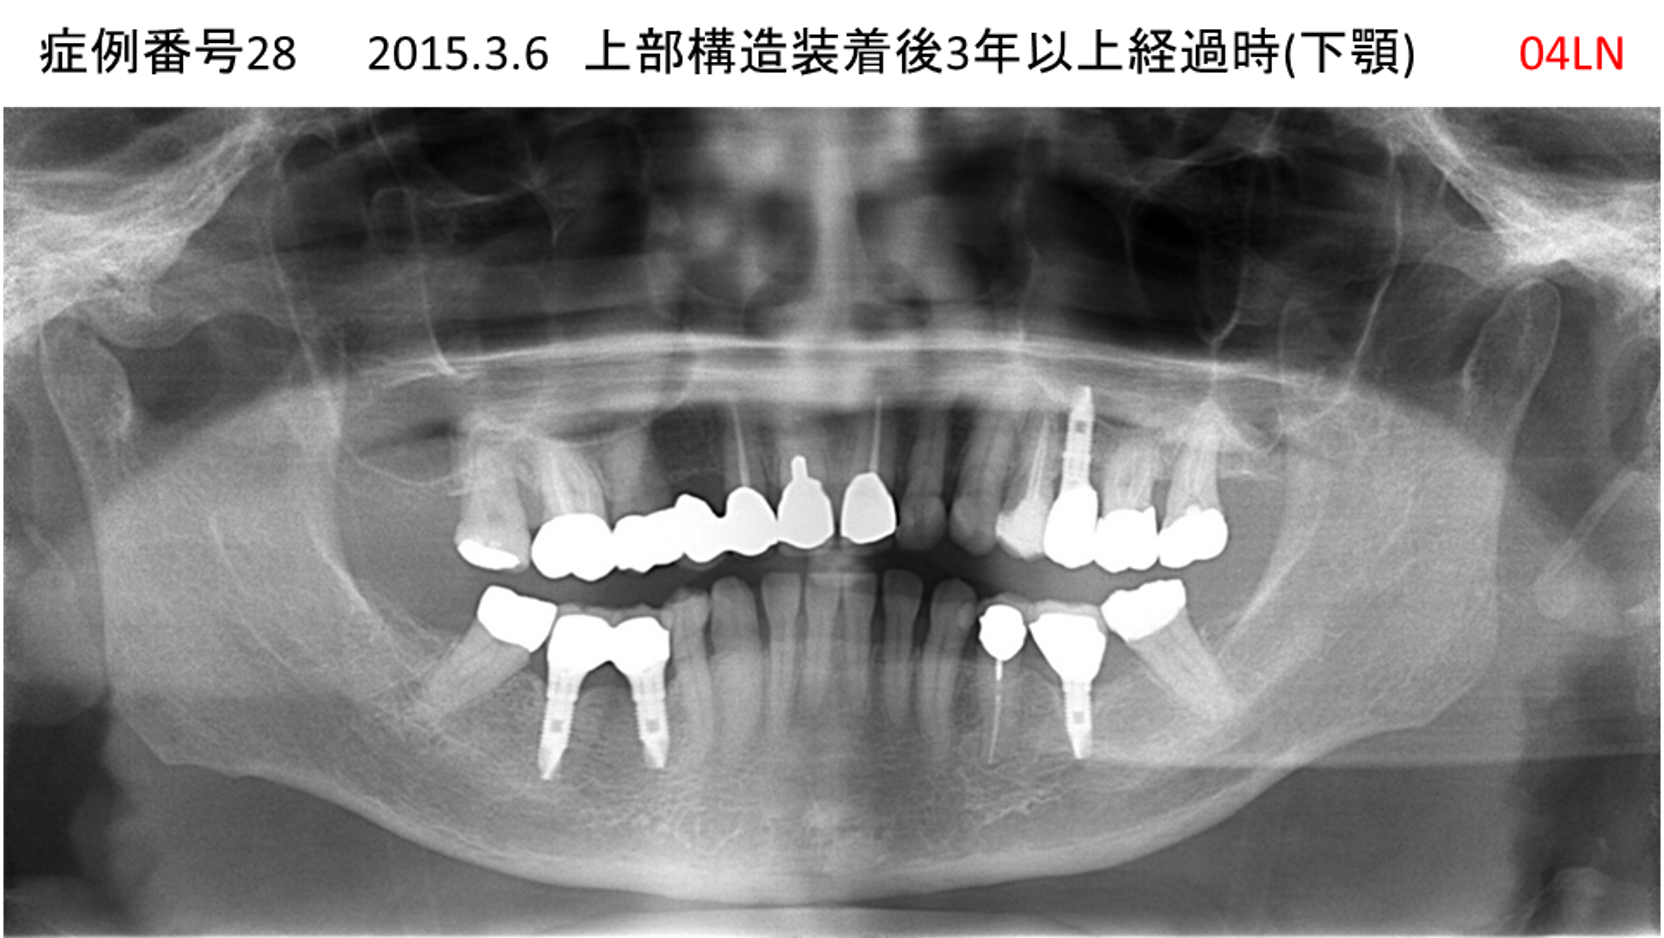

左下の奥歯が痛い患者様のインプラント症例

| 治療名称 |

インプラント |

| 治療費用 |

215万円+税 |

| 治療期間 |

5か月 |

| 患者さんの症状(主訴) |

左下の奥歯が痛い。 |

| 治療内容 |

| 治療結果 |

痛み無く、噛める。 |

| 治療の注意点(リスク/副作用) |

インプラントが壊れたら再治療が必要 |